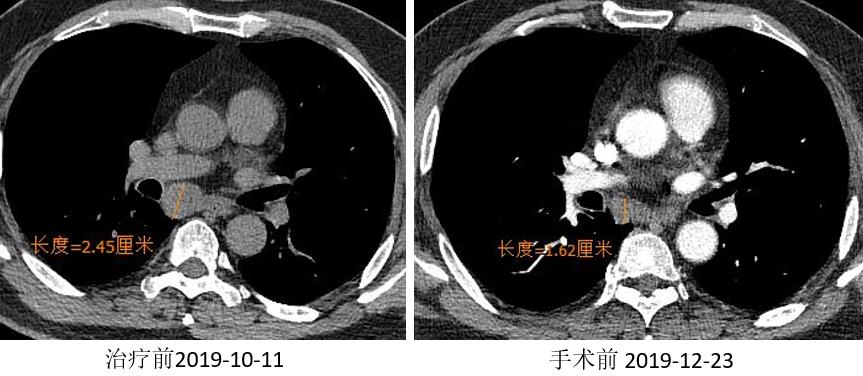

胸部CT

外周淋巴结CT

两周期“信迪利+GP”免疫治疗联合化疗方案。

2019.01.03 行“VATS辅助左肺下叶切除术”。

术后冰冻病理:(左下叶)见少量异型细胞,病灶内见纤维组织伴淋巴组织增生、组织细胞聚集、胆固醇结晶沉积及反应性多核巨细胞,结合病史符合新辅助治疗后反应(MPR)。(第11组淋巴结)肺组织内见纤维组织增生伴炎细胞浸润及组织细胞反应。

疗效评价:MPR。